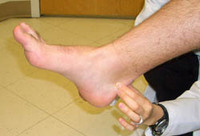

Pressão lateral e medial aplicada na porção anterior e posterior da inserção de Aquiles provoca dor

Do acervo pessoal de James Wang, PhD